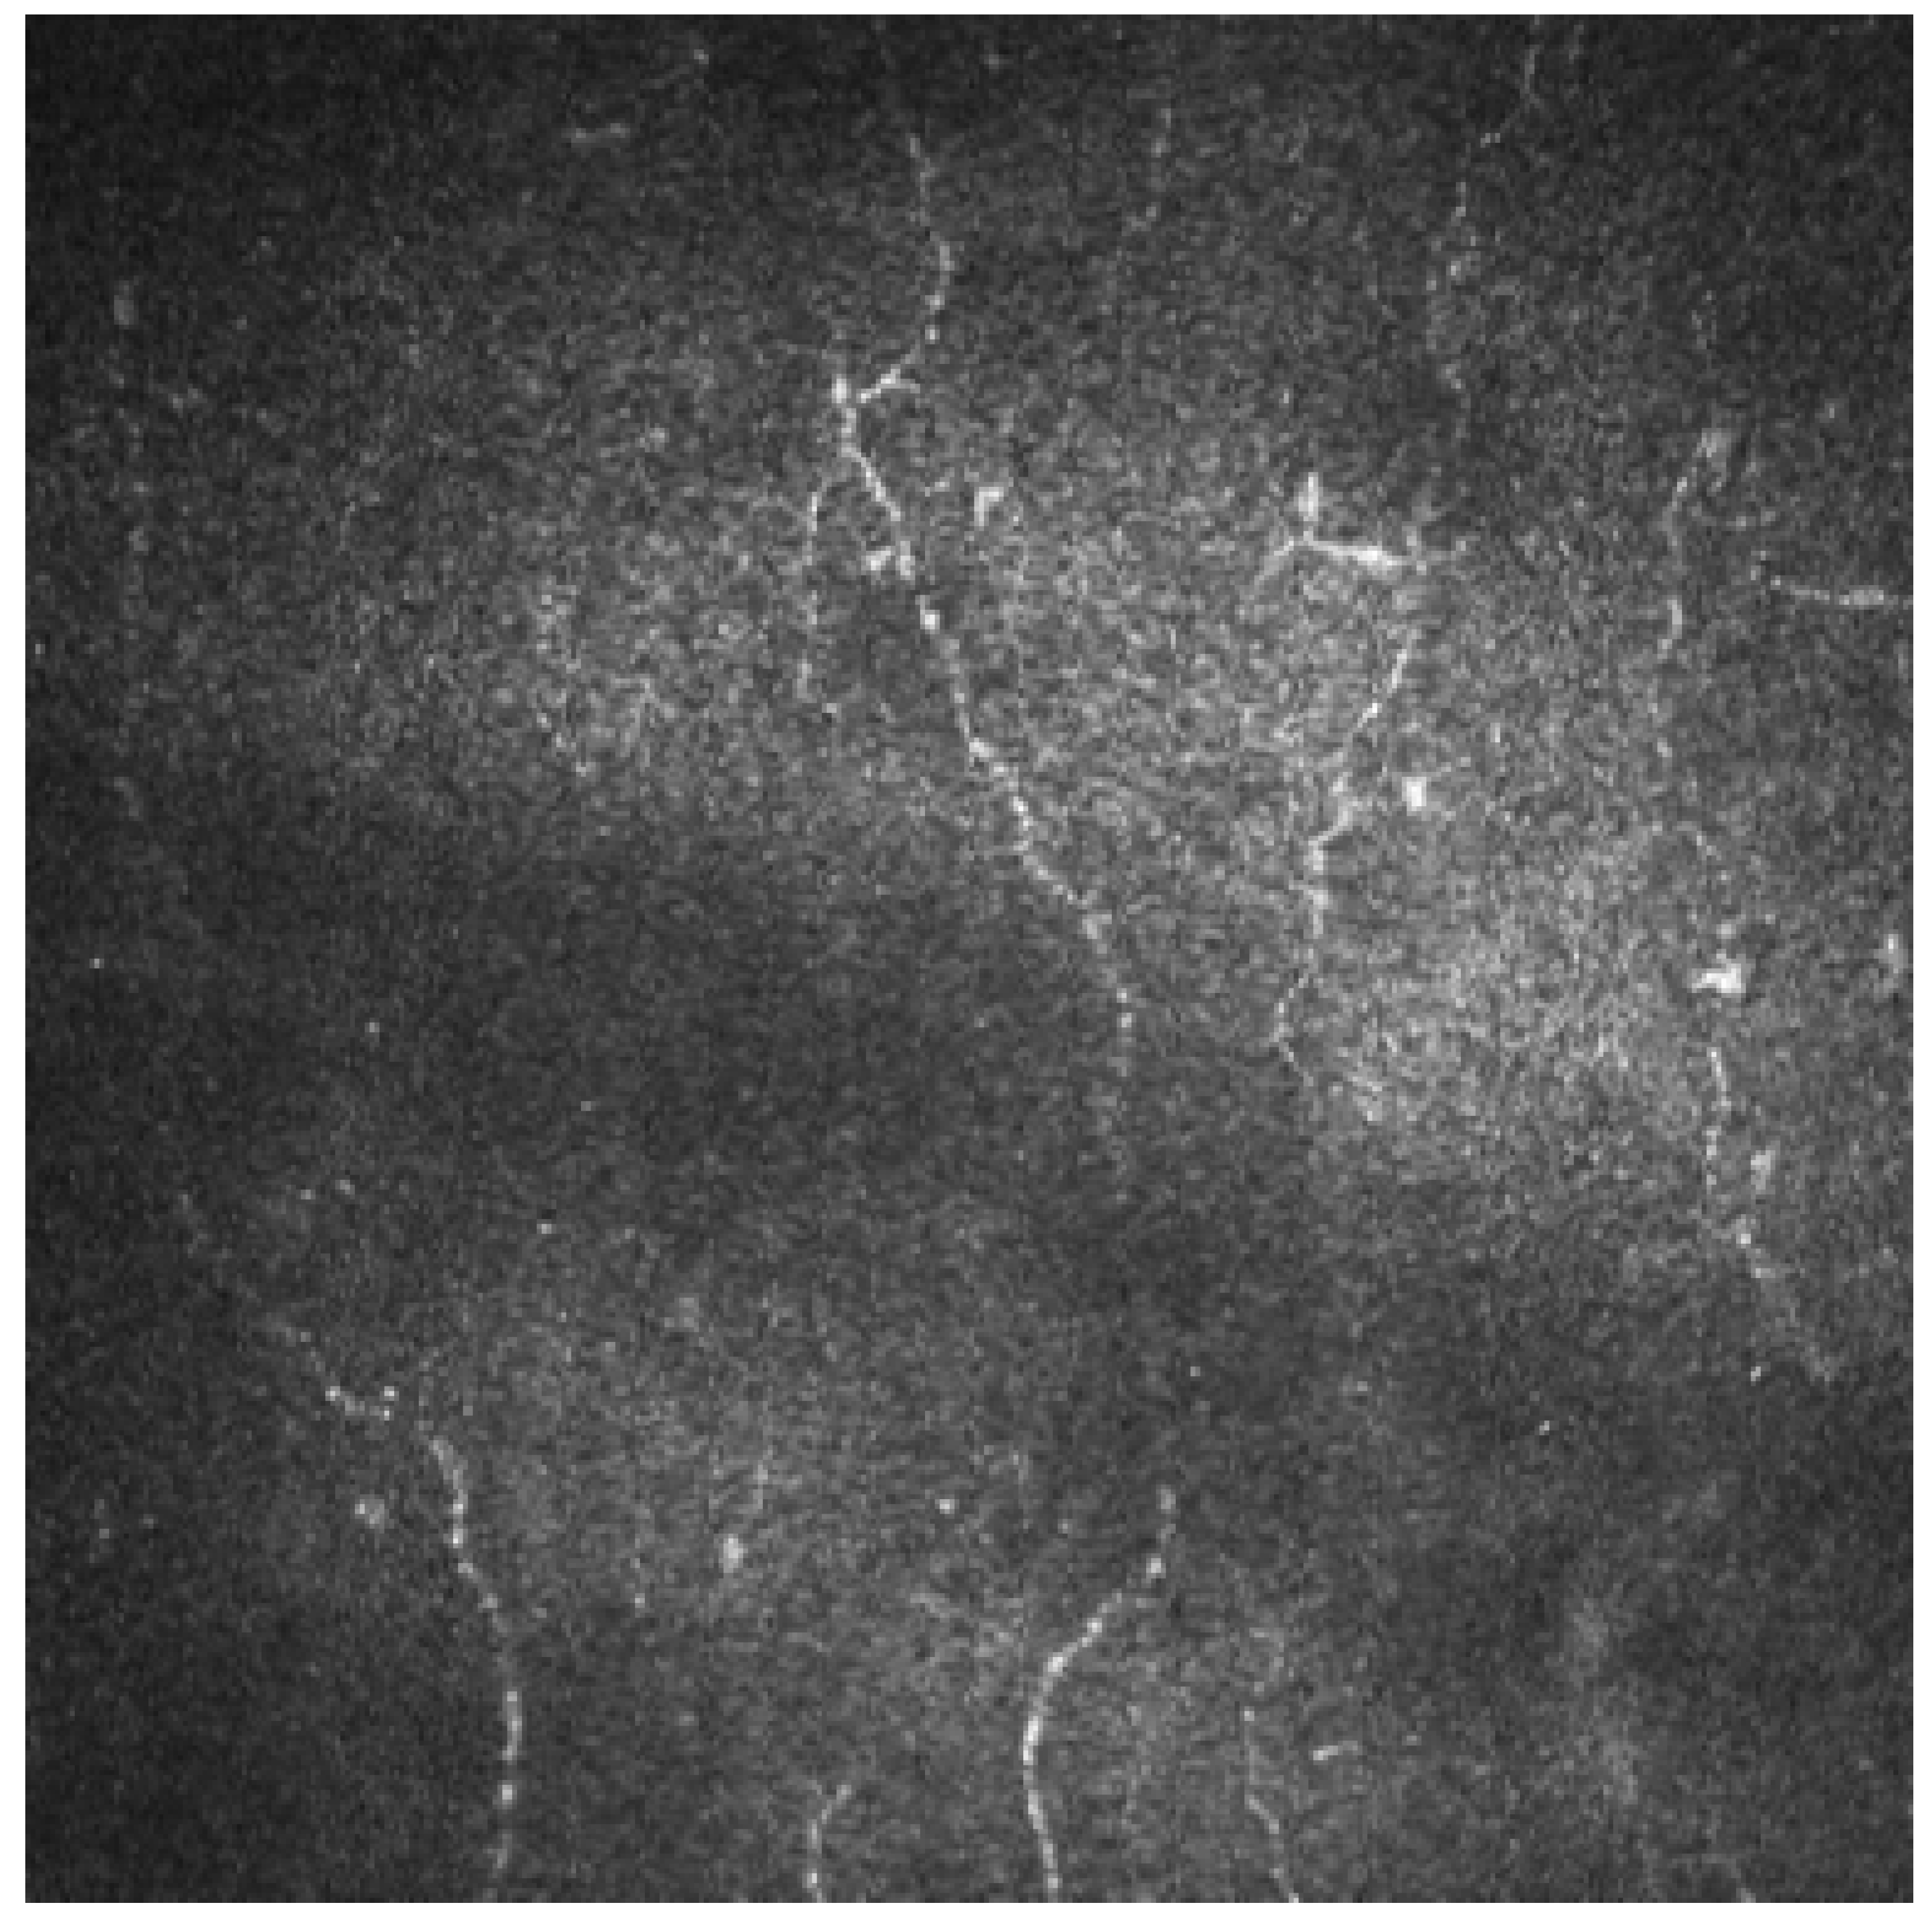

2.4. Corneal Confocal Microscopy